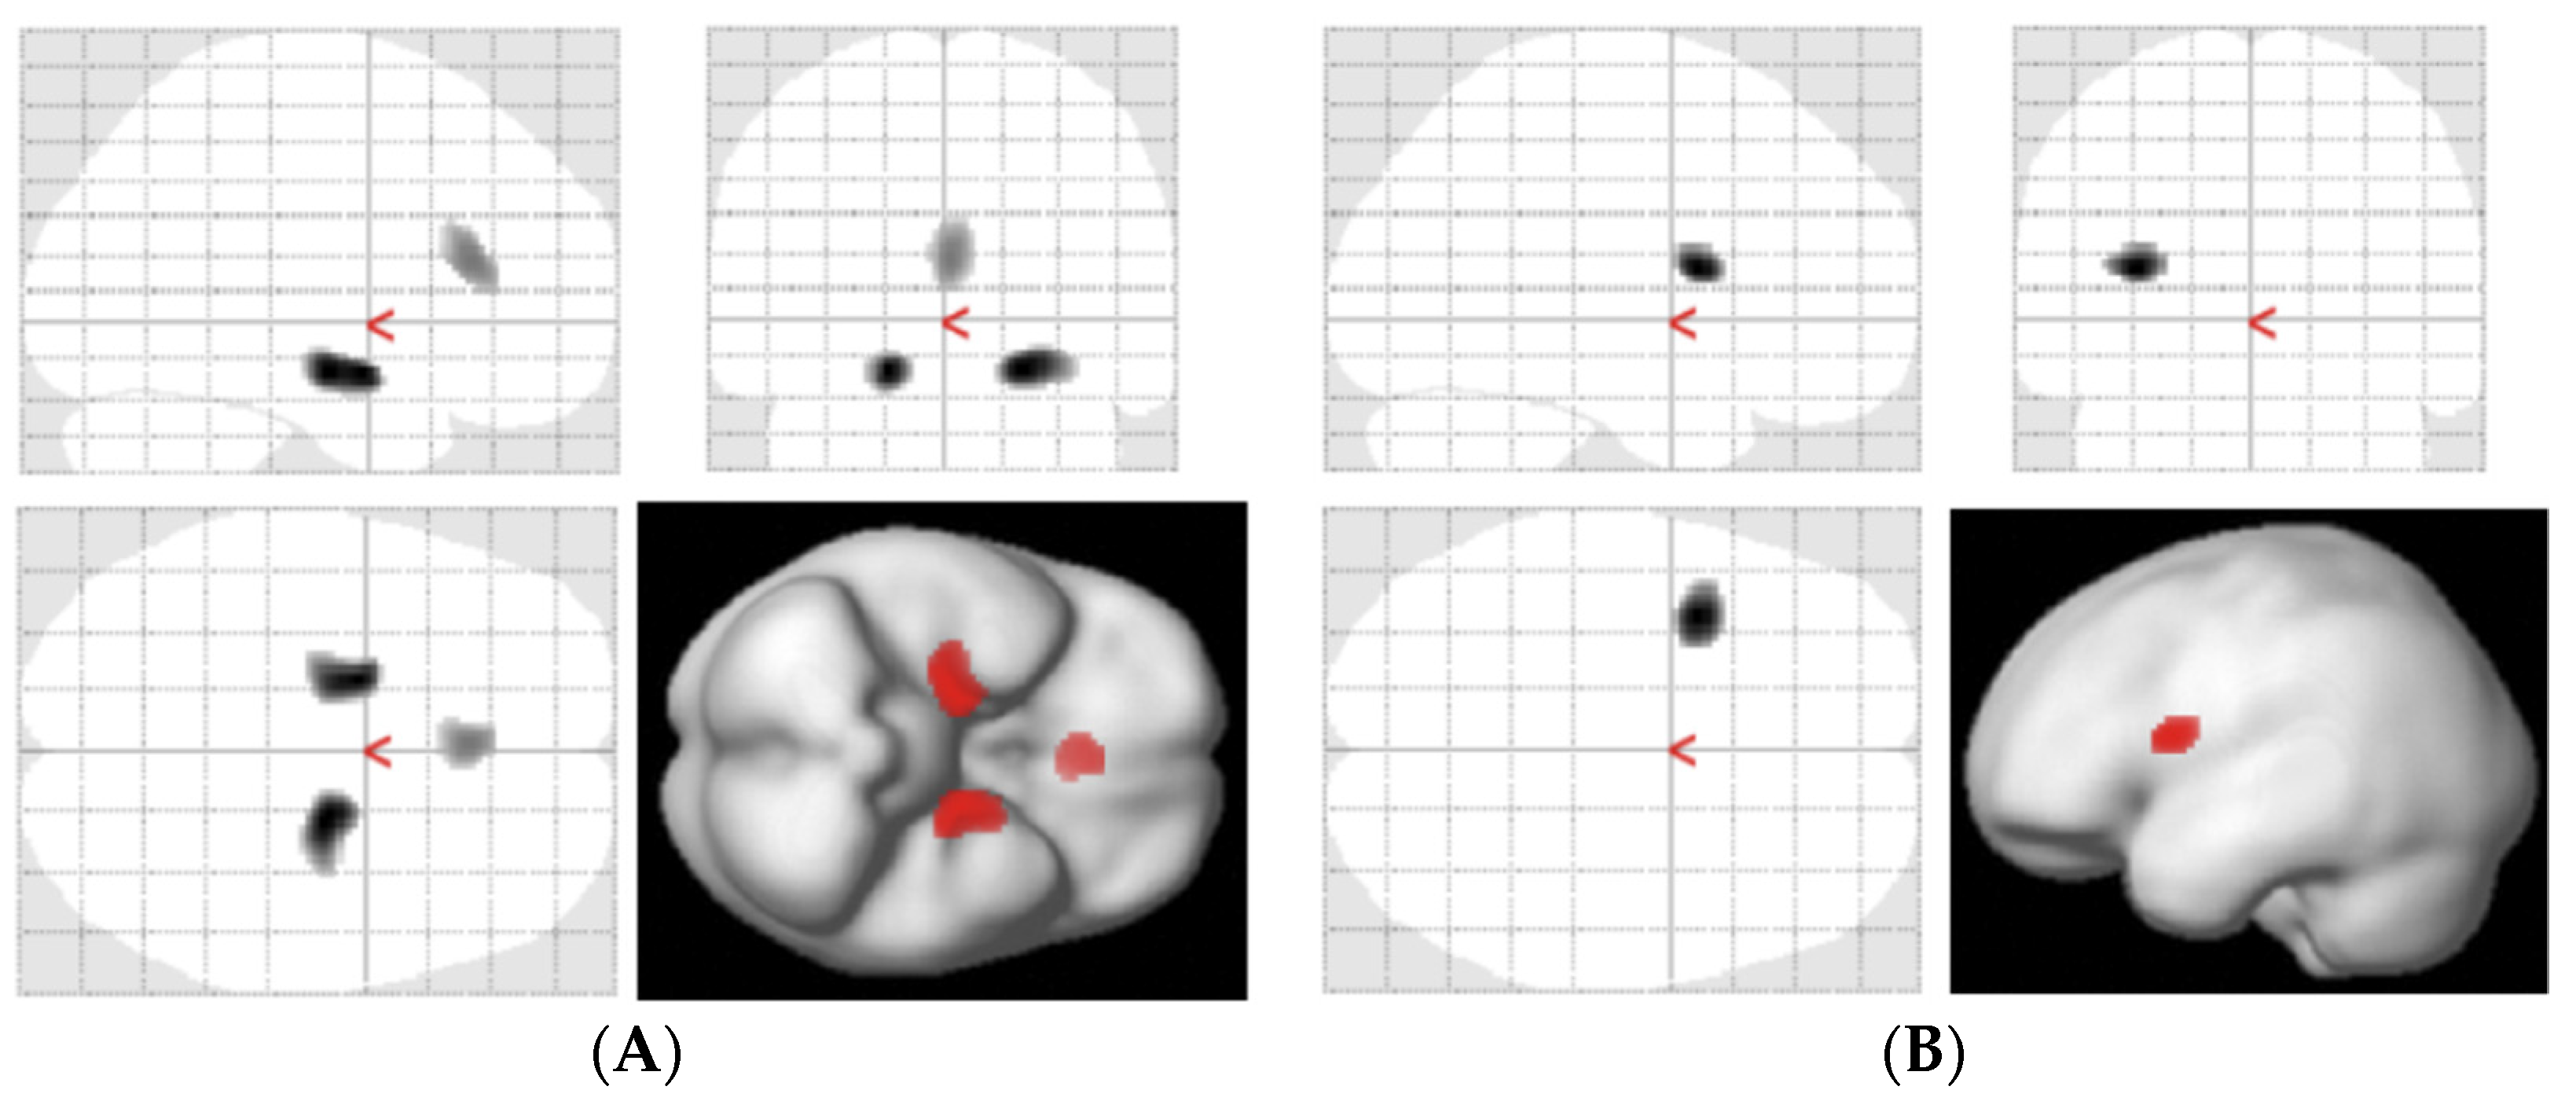

| Hippocampus | 6.37 ± 1.54 | 7.22 ± 2.05 * | ||